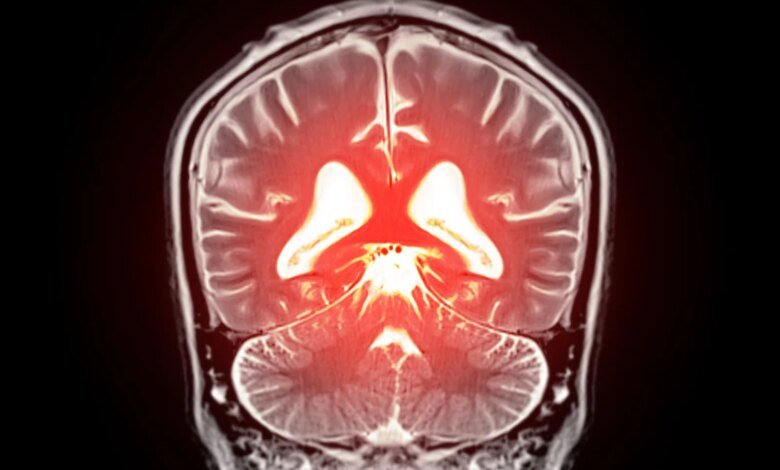

بدأ يتبلور نهج جديد محتمل لعلاج انخفاض تدفق الدم في الدماغ وبعض أشكال الخرف. كشف علماء في جامعة فيرمونت، روبرت لارنر، دكتوراه في الطب بكلية الطب، تفاصيل جديدة حول كيفية تنظيم تدفق الدم في الدماغ وحددوا استراتيجية يمكن أن تساعد في تصحيح المشاكل في الأوعية الدموية في الدماغ. تم نشر بحثهم قبل السريري اليوم (22 ديسمبر) في وقائع الأكاديمية الوطنية للعلوميشير إلى أن استعادة الفسفوليبيد المفتقد في مجرى الدم قد يساعد في تطبيع تدفق الدم العقلي وتخفيف الأعراض المرتبطة بالخرف.

تلقي الدراسة الجديدة، التي تحمل عنوان “PIP2 يصحح اعتلال قناة Piezo1 البطانية”، الضوء على كيفية تأثير Piezo1 على تدفق الدم في الدماغ وتظهر أن حالات مثل مرض الزهايمر ترتبط بزيادة نشاط Piezo1 في الأوعية الدموية. قام فريق البحث بفحص مادة فسفوليبيد موجودة في أغشية خلايا الدماغ تسمى PIP₂. يلعب هذا الجزيء دورًا حاسمًا في إشارات الخلية وفي تنظيم القنوات الأيونية، وهي عملية تتحكم في وقت فتح وإغلاق مسام البروتين في الخلايا.

اكتشف العلماء أن PIP₂ يعمل عادةً كمكابح طبيعية لـ Piezo1. عندما تنخفض مستويات PIP₂، يصبح Piezo1 نشطًا بشكل مفرط، مما يعطل تدفق الدم الطبيعي في الدماغ. عندما أضاف الباحثون PIP₂ مرة أخرى إلى النظام، انخفض نشاط Piezo1 وتم استعادة تدفق الدم الصحي. تشير هذه النتائج إلى أن زيادة مستويات PIP₂ يمكن أن تمثل نهجًا علاجيًا جديدًا لتحسين الدورة الدموية في الدماغ ودعم وظائف المخ.